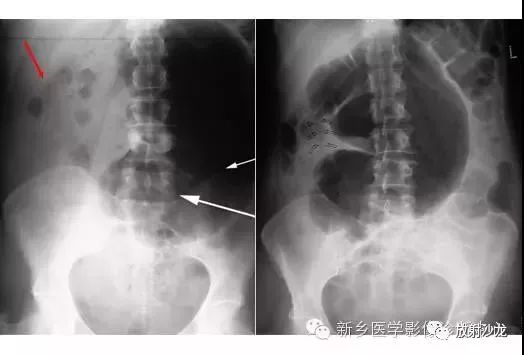

上图符合53岁,女性,肠梗阻所做的腹部平片。发病初所拍图像在左侧,24小时后所拍图像在右侧。是什么原因造成病人梗阻?众多发现都在眼前,不要被箭头影响。

该患者存在一个大的盲肠肠扭转。左侧图像显示一个没有任何可见结肠袋(短箭头),内脏充满大量气体。在升结肠(红色箭头)存在粪便与空气,这表明没有完全阻塞并且一些气体正向远端移动。右图像显示内脏位置的变化,这表明梗阻是非固定的。扭转是由弯曲的箭头所圈出。典型的表现为盲肠头朝向右侧髂窝与肠扭转突出向上朝向左上腹部。